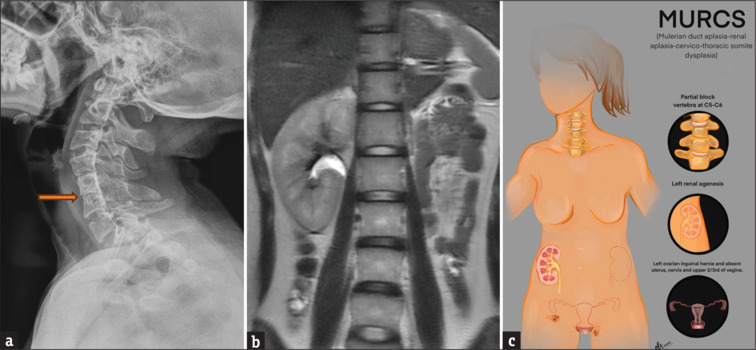

Inguinal hernia in females is an uncommon entity. While most patients present in infancy or early in childhood, only a few cases are diagnosed in adulthood. Most cases of inguinal hernia have small bowel or omentum as its content. Herniation of the ovary or fallopian tube is rare. In our case, an 18-year-old female presented to the outpatient department with unilateral inguinal swelling, which on imaging was found to be ovarian inguinal herniation. This prompted further evaluation. There was an associated absence of the uterus and left kidney, and congenital block vertebrae involving the cervical spine. On probing it was found that she had primary amenorrhoea with normal secondary sexual characteristics. All the findings led to the diagnosis of Mayer Rokitansky Kuster Hauser type II or Mullerian duct aplasia renal agenesis cervicothoracic somite dysplasia (MURCS) with unilateral inguinal ovarian herniation. Mullerian duct aplasia renal agenesis cervicothoracic somite dysplasia (MURCS) present a challenge as they require a multidisciplinary team including gynaecologist, surgeon and psychologist to preserve the ovarian function and help the patient counsel regarding the reproductive outcome and wade through the associated emotional stress.